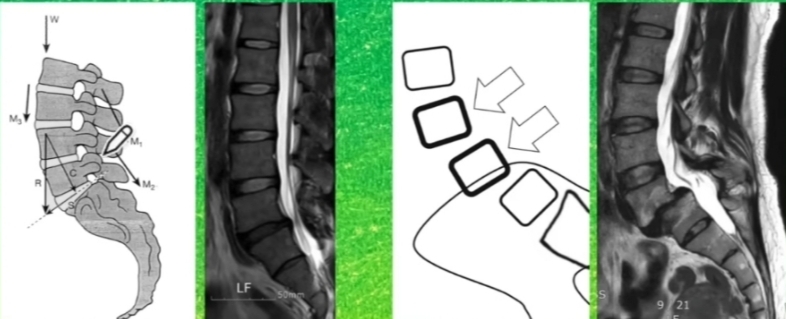

하나의 척추가 인접하는 밑의 척추에 비해 정상적인 정렬을 이루지 못하고 앞으로 빠져있는 상태.

1)협부의 문제로 인해 척추 분리증

: 주로 성장기 때 지속적 스트레스로 발생

2) 퇴행성 디스크

: 나이가 들면서 디스크 손상으로 척추의 불안정성이 높아지면서 발생